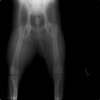

術前正面像

術後正面像

術前に25°であったTPAは、TPLO実施により7°に矯正されました。症例の歩行状態は良好です。